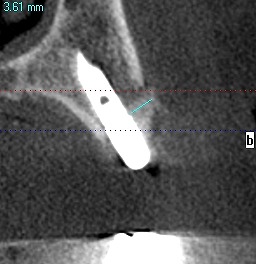

4番のインプラントになります

5番の傾斜埋入にインプラントになります